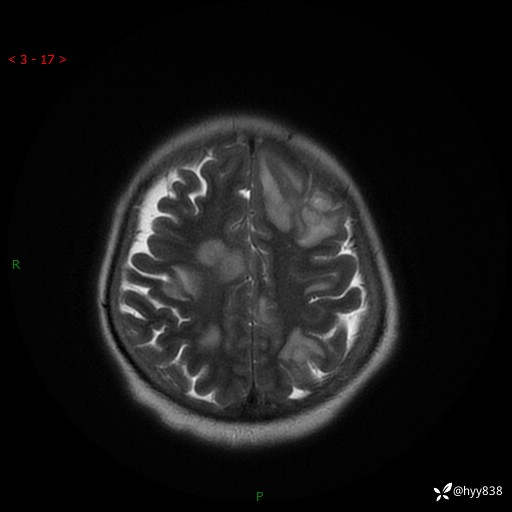

患者性别:女

患者年龄:57岁

简要病史:昏迷入院

颅脑MRI(T2WI+DWI)